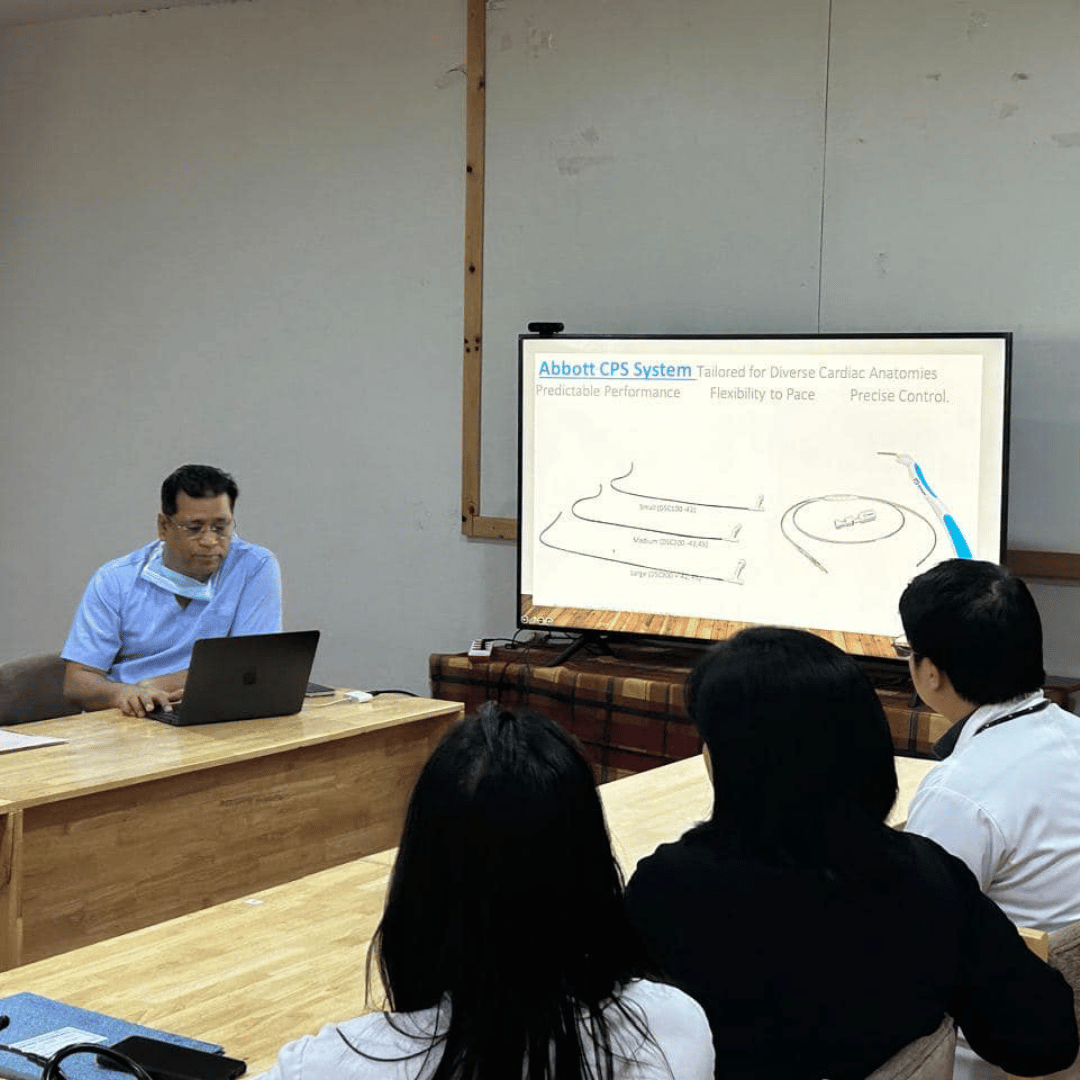

Mentoring young colleagues in their careers is truly rewarding. It was a pleasure to have enthusiastic young operators at our Medica CSP workshop. Additionally, I thoroughly enjoyed scrubbing with Dr. Mahesh at JDWNR Hospital in Thimphu, Bhutan.

CSP workshop at Bankura medical college. It was a great interaction with a highly enthusiastic and skilled team here .